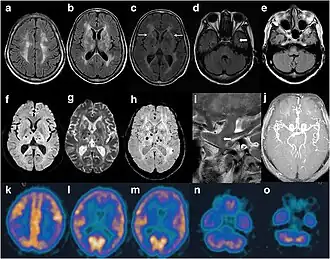

В конце 1990-х удалось идентифицировать мутацию, ответственную за болезнь. Выяснилось, что в кодоне 178 гена PRNP, находящегося в 20-й хромосоме, аспарагин заменён на аспарагиновую кислоту. В результате форма белковой молекулы изменяется, и нормальный белок превращается в болезнетворный прион. Под воздействием аномального приона другие нормальные белковые молекулы тоже превращаются в болезнетворные прионные. Это приводит к накоплению амилоидных бляшек в таламусе, отделе мозга, отвечающем за сон. Вначале амилоидные бляшки вызывают бессонницу, осложнения и летальный исход спустя несколько месяцев[5].